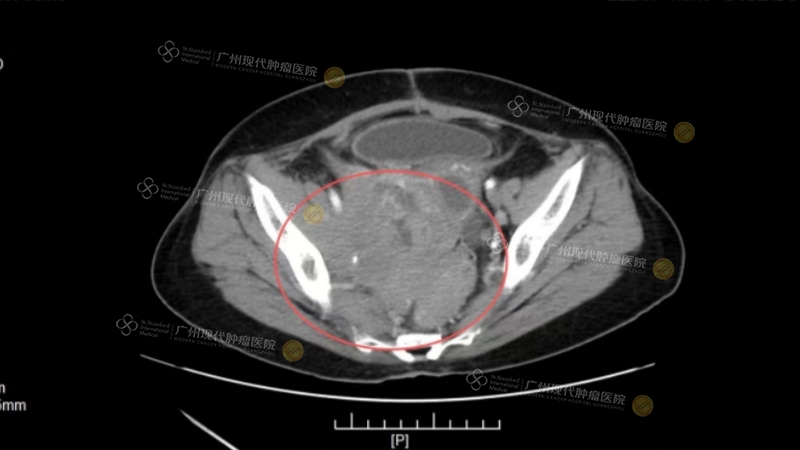

黄作平教授曾参与治疗一位卵巢癌Ⅳ期患者,入院时患者已出现腹腔广泛转移,侵犯肠管,经多线治疗后效果不佳。黄作平团队为其进行基因检测,发现可靶向突变位点,并经过MDT会诊后,治疗策略由此确定:西医采用介入化疗联合靶向治疗,同时配合中医调理改善体质。经治疗后,该患者肿瘤标志物下降,影像学显示肿瘤明显缩小;患者体力恢复,能够正常进食,生活质量大幅提升。

(治疗前CT)